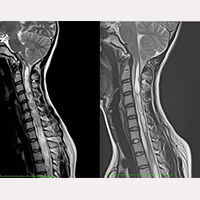

大後頭孔減圧術後の終糸切断手術例

私どもの研究によると、アーノルド・キアリI型症候群の治療で一般的に行われる大後頭孔減圧術は、神経組織に対する大後頭孔の圧迫を軽減することはできますが、一番の原因である、異常な終糸による全神経系への牽引を取り除くことはできません。よって、過去に減圧術を受けた患者さんは終糸切断手術後に病状が改善されたのを感じることができます。